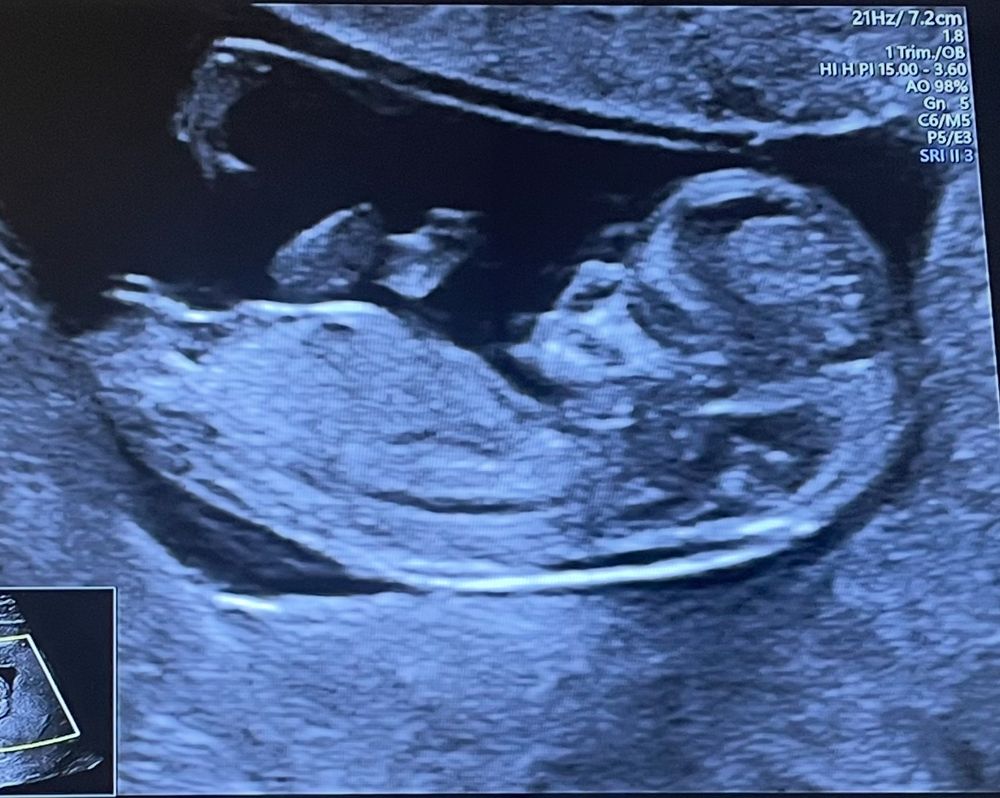

Мальчик или девочка?)

Девчуля, ну очень похоже по бугорку🥰

Lena Sorokina, тут качество снимка хуже и менее понятно. А на фото в посте половой бугорок расположен вдоль позвоночника, это признак девочки. У дочки на первом скрининге точно так же было. У мальчиков на этом сроке бугорок вверх под углом торчит.

Чашка утреннего кофе, ну тут срок 11 недель и 2 дня) может чё еще и вырастит 🤭